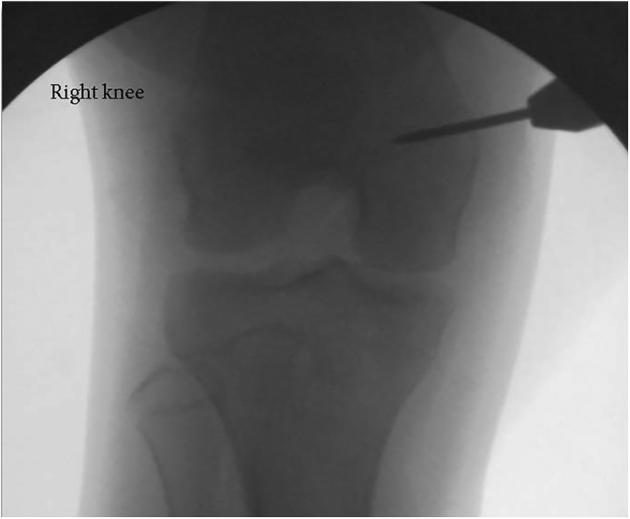

Patellar dislocation is a relatively common pediatric injury, which often results in recurrent patellofemoral instability. An increased tibial tubercle-trochlear groove distance predisposes to patellofemoral instability and can be corrected with a distal realignment procedure. Soft-tissue distal realignment procedures must be used in the pediatric population to avoid the risks of premature physeal closure associated with tibial tubercle osteotomies. Several soft-tissue distal realignment procedures have been described, with no consensus as to the optimal technique. When combined with medial patellofemoral ligament reconstruction, distal realignment procedures can restore patellofemoral stability through the entire flexion arc. This article describes a modification of the Grammont distal patellar realignment procedure in conjunction with medial patellofemoral ligament reconstruction for the management of pediatric patellofemoral instability.

髌骨脱位是一种相对常见的儿科损伤,常导致复发性髌股关节不稳定。胫骨结节 - 滑车沟距离增加易引发髌股关节不稳定,可通过远端重排手术进行矫正。在儿科人群中必须采用软组织远端重排手术,以避免与胫骨结节截骨术相关的过早骨骺闭合风险。已经描述了几种软组织远端重排手术,但对于最佳技术尚无共识。当与髌股内侧韧带重建相结合时,远端重排手术可在整个屈曲弧范围内恢复髌股关节稳定性。本文描述了Grammont远端髌骨重排手术的一种改良方法,结合髌股内侧韧带重建用于治疗儿科髌股关节不稳定。